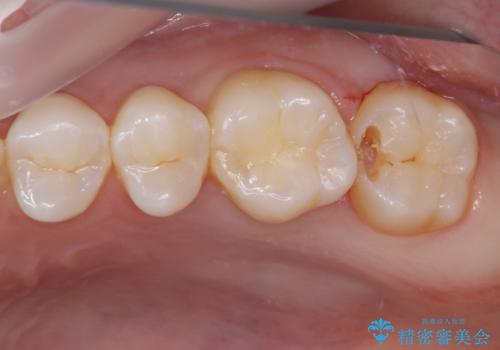

- 奥歯にフロスが引っかかるようになり、虫歯ではないかとのことで来院された患者様です。

レントゲン写真より、1番奥の歯に虫歯があることが分かりました。

奥で目立たないことから、虫歯の再発リスクが最も低く、咬合力による歯への負担も少ないゴールドインレー(PGAインレー、白金加金インレー)にて修復治療をすることとしました。